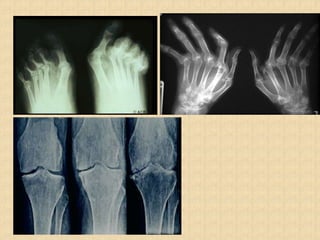

Radiographic Features

• Peri-articular osteopenia

• Uniform symmetric joint space narrowing

• Marginal subchondral erosions

• Joint Subluxation

• Joint destruction

• Collapse

• Ultrasound detects early soft tissue lesions.

• MRI has greatest sensitivity to detect synovitis and

marrow changes.

Moll And Wright Clinical Pattern

• Including 5 clinical patterns:

Asymmetric mono-/oligoarthritis (~30% [range 12-

70%])

Symmetric polyarthritis (~45% [range 15-65%])

Distal interphalyngeal (DIP) joint involvement (~5%)

Axial (spondylitis and Sacroiliitis) (HLA-B27) (~5%)

Arthritis Mutilans (<5%).

CASPAR Criteria For Diagnosis

• Inflammatory articular disease (joint, spine, or

entheseal)

• With 3 points from following categories:

 Psoriasis: current, history, family history.

 Nail dystrophy.

 Negative rheumatoid factor.

 Dactylitis: current, history.

 Radiographs:(hand/foot) evidence of

osteolysis, juxta-articular new bone

formation(pencil in cup).

• Specificity 98.7%, Sensitivity 91.4%